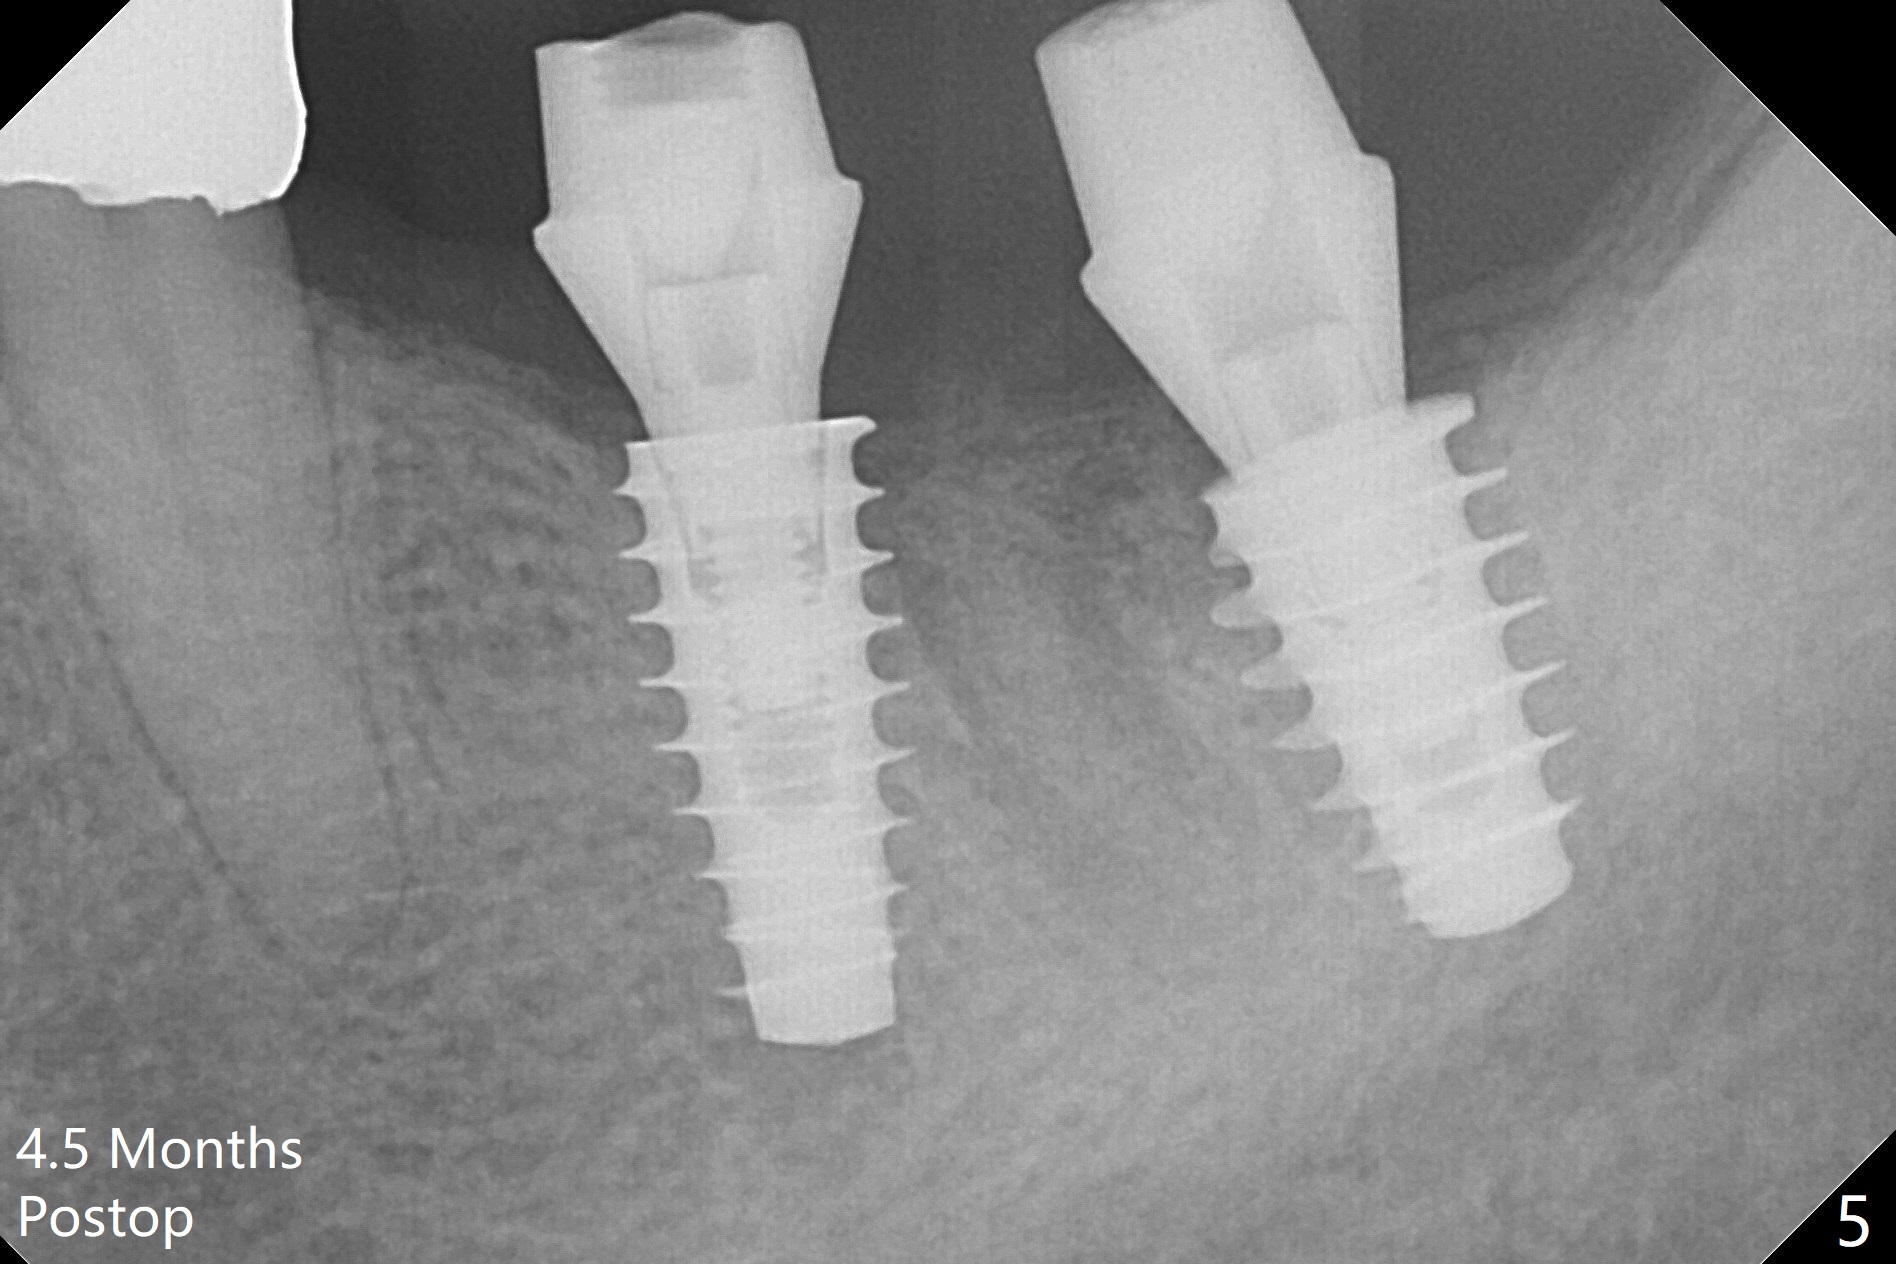

A drawback of placing an implant in the distal socket of the 2nd lower molar is closer to the Inferior Alveolar Canal. The implants seem to have osteointegrated 4.5 months postop (Fig.5). While the ridge at #19 appears to be wider than preop (as compared to Fig.1), that at #18 seems to be atrophic 5 months postop (Fig.6 * (1 week post cementation)). The distal implant placement at #19 may increase possibility of abutment screw loosening during functioning (Fig.7 *). When the patient returns for periodic exam 1.5 months post cementation, loose contact between the implant crowns is noted (Fig.8). The bony trabeculae form between the 2 implants crestally 12 months postop, i.e., 7 months post cementation (Fig.9). The loose contact between the 2 implants is corrected 14 months post cementation.